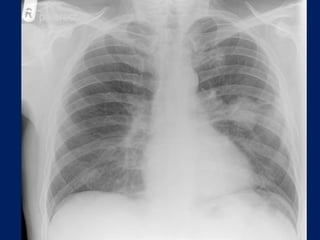

Chest radiographs may show the following:

• Pulmonary nodule, mass, or infiltrate

• Mediastinal widening

• Atelectasis

• Hilar enlargement

• Pleural effusion

Lung Cancer:

Findings on Chest X-ray

• Nodule (< 3cm) vs. Mass (>= 3cm).

– Location:

• Peripheral (Adenocarcinoma) vs.

• Central (Squamous).

– Single or multiple (metastases).

• Endobronchial obstruction.

– Atelectasis of lobe or lung.

– Pneumonia.